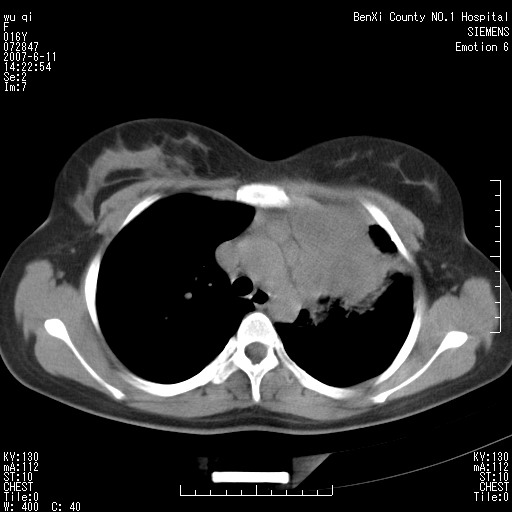

女.16、咳嗽、乏力、消受,食欲差,一个月余,无咯血,一个月前有发热。经抗炎治疗发热消失,仍咳嗽。平扫ct值34-45hu,增强后60-78hu明显强化,另外为了大家方便阅片,简单提下自己意见,纵隔内淋巴结肿大,左肺片影,其内密度不均,增强扫描明显强化,左肺上叶支气管可见支气管气象。尖段闭塞。冠状位可见左侧锁骨下静脉受压下移。请大家会诊,分析。

左上肺野纵隔旁软组织密度块影,增强欠均匀性强化,其内可见血管影穿梭,肿块周围之肺组织及纵隔气管均有不同程度受压改变;定位及定性均有困难...根据病史考虑以下几点:1.来源纵隔可能性较大,腺瘤?淋巴性肿瘤?其他?2.肺组织来源?左上肺占位(ca)?3.不排除原发性综合征可能?

肺不张会引起纵隔结构向患侧移位,而该病例纵隔是向右侧移位,且左侧锁骨下静脉受压移位,均提示病灶位于纵隔内。我感觉象是淋巴瘤,左肺病灶是因为阻塞性肺炎引起的。

2、左上肺我认为是个不张的肺,仔细看左上肺体积有点缩小

3、不张的原因我认为是淋巴结压迫所导致,支气管内膜结核一般有下肺的播散灶

看过病例,肿块位于左侧胸膜顶和上纵隔,呈巨大不规则形软组织密度,边缘不清楚,和上纵隔诸结构不好分界,并可见肿大淋巴结影,左上叶支气管尚通畅,但上叶肺组织可见压迫性不张和膨胀不良。肿块内部可见一条明显的粗大血管影,经多层面追踪,应该是左侧锁骨下静脉。从以上表现来看,肿块的起源应该是在肺外,大致来源于胸膜顶部,向下、内生长。增强扫描,肿块内部可见多发血管分支,证明肿块血供较为丰富,从这一点上,比较符合间叶组织来源的恶性肿瘤,淋巴瘤往往表现为多发肿大淋巴团,但增强扫描内部出现迂曲血管的几率比较低,我觉得不是太象。间叶组织类别非常多,该类肿瘤只靠影像学很难鉴别,经皮穿刺活检不失为最好的方法,可以首先考虑。

定位定性理由:1 斜裂到哪里去了?明显的前上移位了.2 原"左上肺区域"透光度明显增高,肺纹稀疏,为肺气肿征象.3不是全上肺不张,而为固有上叶,可惜楼主的冠位图未明显显示.4 左下肺背段可见结节灶,紧贴脊柱旁,再仔细看看.5 胸膜改变显示支持是炎性病变.6那根血管我也仔细观察了,浓度同动脉,近端较粗,应为肺动脉,包括实变肺内的血管分支都应为肺动脉分支.7 实变内明显不均强化,更加支持炎性病变.8淋巴结肿大以弓旁为主,轻度均匀强化,中纵隔内未见明显淋巴结,面此区的淋巴肿最多见于结核;9实变近端无明显块影而不支持腔内肿瘤,虽然无典型的支气管狭窄直接征象.10 为什么纵隔向患侧移位不明显?因为肺容积缩小不是太显著,更多的是肺泡内较多渗出导致如此.11 实变外围的条片影从形态看不象纵隔肿瘤所致的压迫性肺炎,如为压迫应紧绕肿块环形分布.14 与纵隔结构有明显分界,而且从重组图像看病灶主体更象楔变而非肿块,有哪一种肿瘤可以导致下缘如此平直?